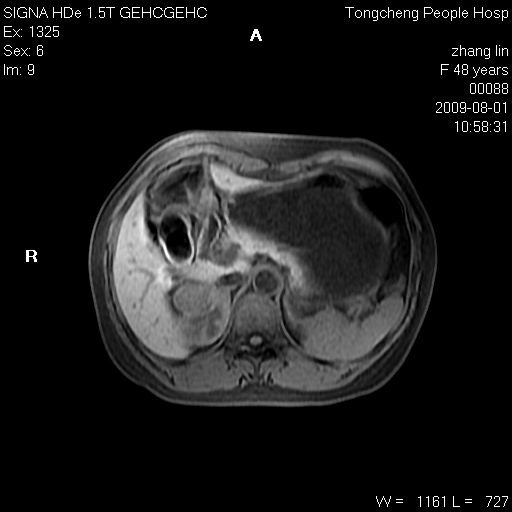

女,48岁。健康体检,彩超发现右肾占位性病变。平素健康。

临床诊断:右肾占位性病变,性质待定(囊肿?肿瘤?)。

上中腹部mr平扫+增强扫描,图像如下:

右肾上极见一类圆形病灶,t1wi呈等信号t2wi呈等高混杂信号,三期增强无强化,边界清---考虑囊肿出血。

同反相位均表现为等信号,病变无强化,考虑含蛋白的囊肿可能,弥散加权相或许有些帮助,